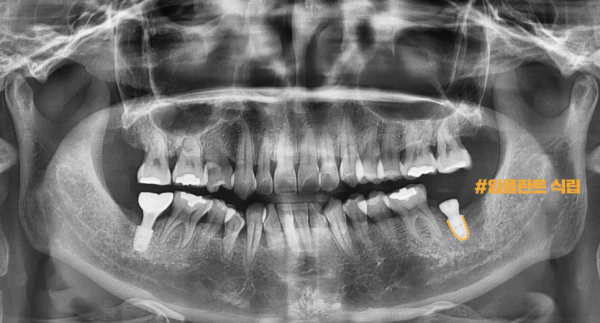

환자분의 문제가 있던 치아는 발치하고 이렇게 임플란트가 안전하고 정확하게 심어졌습니다.

지르코니아 크라운으로 마무리하였답니다.

이 환자분은 양쪽 아래 어금니쪽에 문제가 있었기 때문에

오른쪽 치료한 부분이 잘 적응이 된 후에 반대편을 치료하기로 하였답니다.

The patient's problematic tooth was removed and the implant was safely and accurately planted.

It's finished with zirconia crown.

This patient had a problem with both lower molars

We decided to treat the other side after the right side of the treatment is well adapted.

8개월의 시간이 후른뒤에 환자분의 왼쪽 아래 어금니 역시 저희 태평역치과 더서울치과에 찾아오셔서

치료가 진행되었으며, 역시 디지털 임플란트 방식으로 안전하고 정확하게 심어졌습니다.

After 8 months, your lower left molar also came to Taepyeong Station Dental Clinic, The Seoul Dental Clinic

Treatment has progressed and was also safely and accurately planted with digital implants.